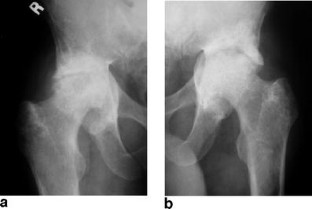

Fibrogenesis imperfecta ossium: MR imaging of the axial and appendicular skeleton and correlation with a unique radiographic appearance

We describe a distinctly unusual MR appearance of the cancellous bone never before described in a patient with biopsy-proven fibrogenesis imperfecta ossium.

Fig. 4